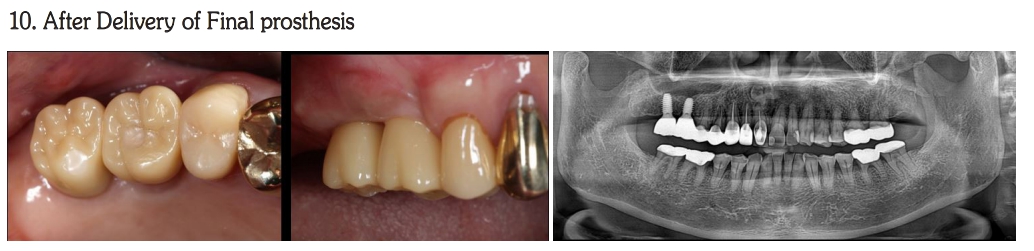

Implant Prosthodontic Rehabilitation with bright Tissue level Implant & Digital abutment